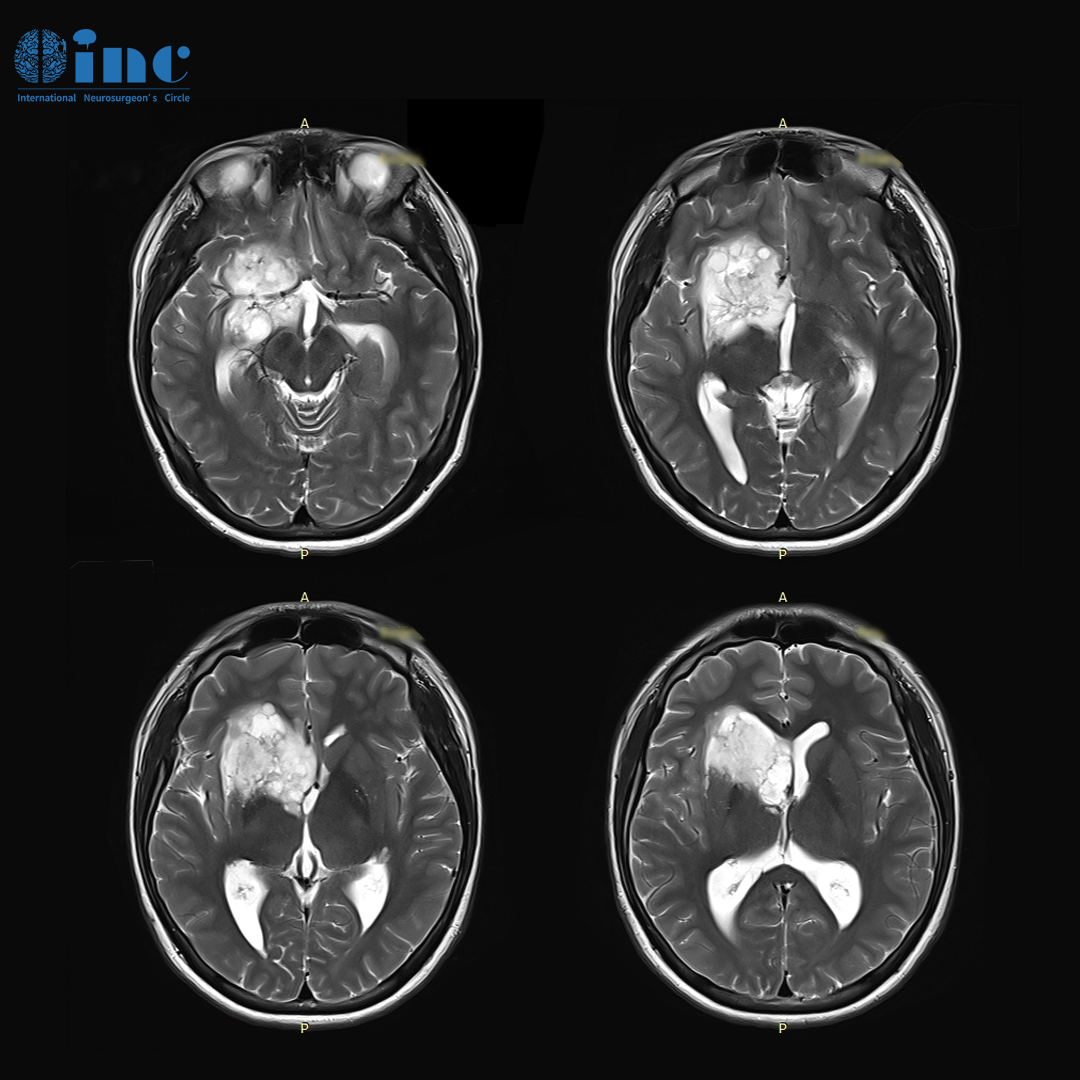

体检结果带来重大发现

一切始于阿杰的一次学校常规体检。他被检查出"颅内占位性病变",这一结果给全家带来巨大冲击。不久后,阿杰在父母陪伴下前往医院进一步检查,被诊断为"右额、颞、基底节区、侧脑室前角区占位病变,胶质瘤可能性大"。

看到影像上显示的巨大肿瘤,阿杰父母心情沉重。肿瘤性质为良性还是恶性?是否能够手术?手术后是否会出现后遗症?这些问题在他们脑海中浮现。医生的一句话缓解了部分焦虑:"别担心,这很可能是低级别胶质瘤。只要实现最大程度安全切除,低级别胶质瘤通常预后良好,生存期相对较长。"但医生随后补充:"如果现在不抓紧手术,不排除肿瘤生长或恶化的可能性。目前孩子没有症状,但等到肿瘤增大,后续发展将难以预测。"